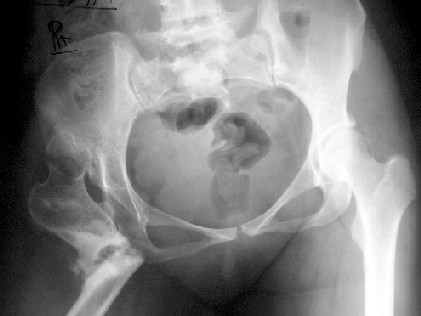

A 30-year-old female patient, presented with pain and limping post hip surgery and lengthening using Ilizarov technique 2 years duration.She said she had only limping preop. now she has painful limping and she can't walk without using walking aid.

Her X-ray --> non-union at the osteotomy site,pelvic tilt,bowing of the femur.clinically painful mobile pseudoarthrosis, LLD =4CM. Could those colleagues using such type of osteotomy Ilizarov method give us the clues how to treat such problems?Does this type of osteotomy still practiced by the group?Dr.Freih Odeh Abu Hassan,M.D(Orth.), F.R.C.S(Eng.), F.R.C.S.(Tr.&Orth.),Asst.Professor of Orthopedics Surgery,Jordan University - Amman.

Это вариант лечения по Илизарову при врожденном вывихе бедра у взрослых. Основан на методе Шанца (создание упора под впадину - вот как раз где не срослось), дополненный удлинением дистально с восстановлением механической оси бедра.